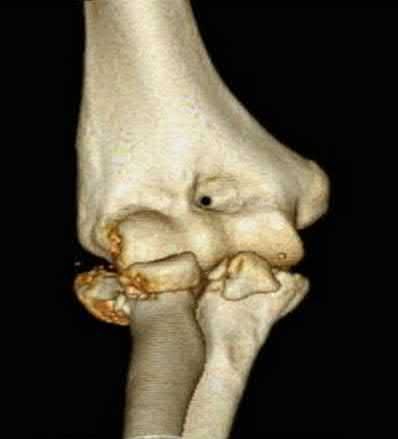

A 28-year-old male sustains a severe hyper-dorsiflexion injury to his ankle in a motor vehicle accident, resulting in a Hawkins Type III talar neck fracture. Which of the following arteries provides the predominant blood supply to the body of the talus, placing it at significant risk for avascular necrosis in this injury?

The artery of the tarsal canal, which is a branch of the posterior tibial artery, provides the dominant blood supply to the talar body. In a Hawkins Type III fracture (talar neck fracture with subtalar and tibiotalar dislocation), the blood supply from the artery of the tarsal canal, the artery of the sinus tarsi, and capsular vessels are disrupted, leading to an avascular necrosis (AVN) rate approaching 100%.